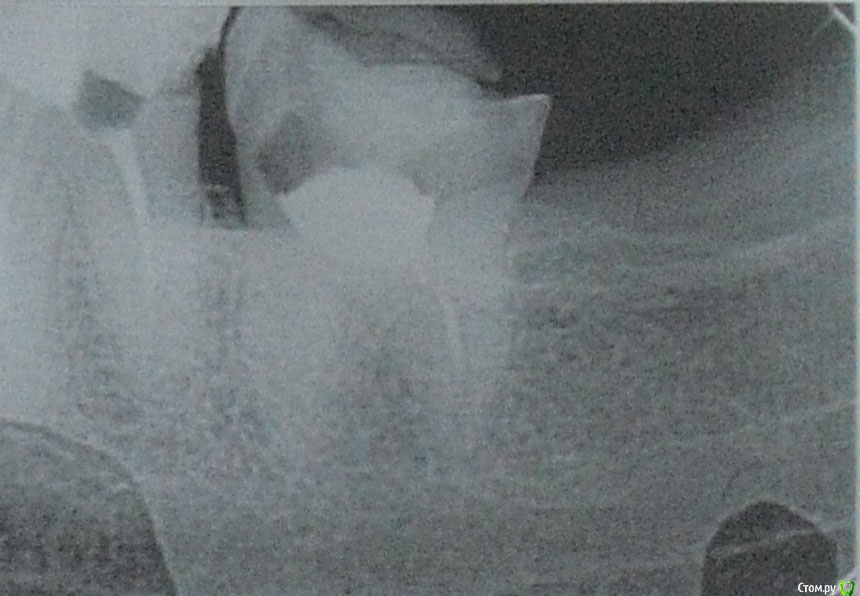

Здравствуйте! две недели назад был флюс.Хирург сделал надрез, дренаж не ставил, выписал антибиотики полоскание содой с солью. Отек сошел, но не полностью - десна немного увеличена. Все это время выходил гной. Дня три гной не выходит, но там белая фигня какая-то как налет, но как будто под кожей. Я не понимаю, т ли не долечили то ли что. Хирург говорит что нужно удалять 8 зуб что причина в кармане (это он определил по рентгену) и что иначе десна не пройдет. Но яне понимаю откуда там карман мне никогда туда пища то не забивалась. Поранить грубой щетиной щетки я реально могла но чтобы там остатки пищи гнии странно как-то.... на рентгене фото 1 это 7 зуб, а на фото 2 это  7 и 8 зуб. Зуб мудрости у меня не болит! Неужели без удаления никак? там действительно по рентгену карман? Подскажите пожалуйста уважаемые доктора! И еще момент хирург предлагает в качестве анастезии убистезин! говорит что он лучше обезболивает а так как идет воспалительный процесс то лидокаин с адреналином могут плохо подействовать и будет больно! Я постоянно принимаю анаприлин, он нормально сочетается с убистезином? раньше мне кололи лидокаин садреналином и я нормально переносила. Что скажете про убистезин, заранее большое спасибо!

post-58333-0-77537500-1565033850_thumb.jpg